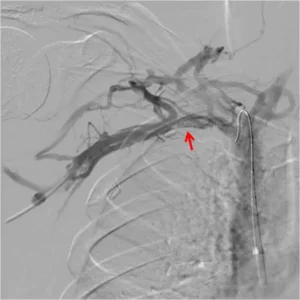

Other than clinical presentation, the classic imaging study to make the diagnosis is an ultrasound examination. The ultrasound will show the extensive clot. But once we start treatment with anticoagulation, we usually aim to follow with invasive therapy. This includes thrombolysis of the blocked vein. Then, we can supplement the diagnosis with provocative maneuvers under angio, to look for venous compression.